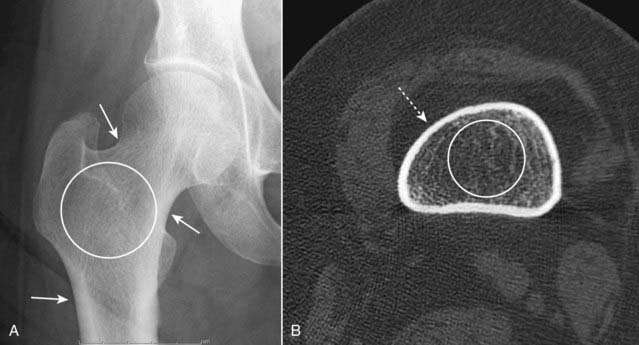

Figure 21-1 Normal appearance of bone.

A, This is an anteroposterior view of the hip. When viewed in tangent, the cortex is seen as a white line, varying in thickness in different parts of the bone (solid white arrows). In the medullary cavity, cancellous bone is seen to contain an interlacing network of trabeculae (white circle). B, An axial CT scan through the proximal femur. The entire 360° circumference of the cortex (dotted white arrow) is seen surrounding the less-dense medullary cavity containing both bony trabeculae and fat (white circle). The image is optimized to display bone so that the muscles and subcutaneous fat are less well seen.